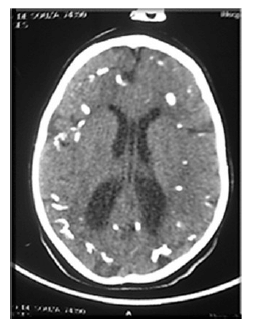

Recém-nascido de 5 dias de vida, do sexo masculino, nasceu de parto vaginal, com as seguintes características: IG = 36 semanas, PN = 2.380 g (AIG), Apgar 7/8, PC = 29 cm. A mãe não realizou pré-natal e apresenta o seguinte perfil: G3P2A1, 28 anos de idade, tabagista de 10 cigarros ao dia, nega consumo de álcool e de drogas ilícitas. O RN ficou internado desde o nascimento por sepse precoce. Após três dias de vida, seu caso evoluiu para crise convulsiva. Realizou tomografia de crânio, apresentada na imagem.